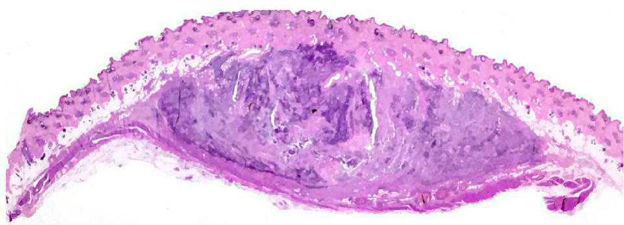

La diagnosi definitiva delle neoplasie surrenaliche, necessita purtroppo una valutazione istologica. Gli aspetti clinici, i dosaggi ormonali e i riliev di diagnostica per immagini possono ovviamente indirizzare verso un incidentaloma non secernente, un tumore secernente adrenocorticale, un feocromocitoma o una metastasi. Tuttavia la conferma definitiva richiede una biopsia. L’esame citologico ha dimostrato una elevata accuratezza nella distinzione di neoplasie corticali VS midollari. Ma quando è rischioso farlo?

L’esame citologico delle neoformazioni surrenaliche d’altra parte ha dimostrato una elevata accuratezza (90-100%) nella distinzione tra proliferazioni corticali (imagine in alto) e midollarii-feocromocitoma (immagine in basso). Sebbene non permetta con certezza di differenziarne forme maligne da benigne, il conoscere anticipatamente se una neoplasia sia corticale o midol

lare, permette al clinico di prendere possibili precazioni in caso di chirurgia, che potrebbe scatenare crisi ipertensive nel caso di un feocromocitoma.